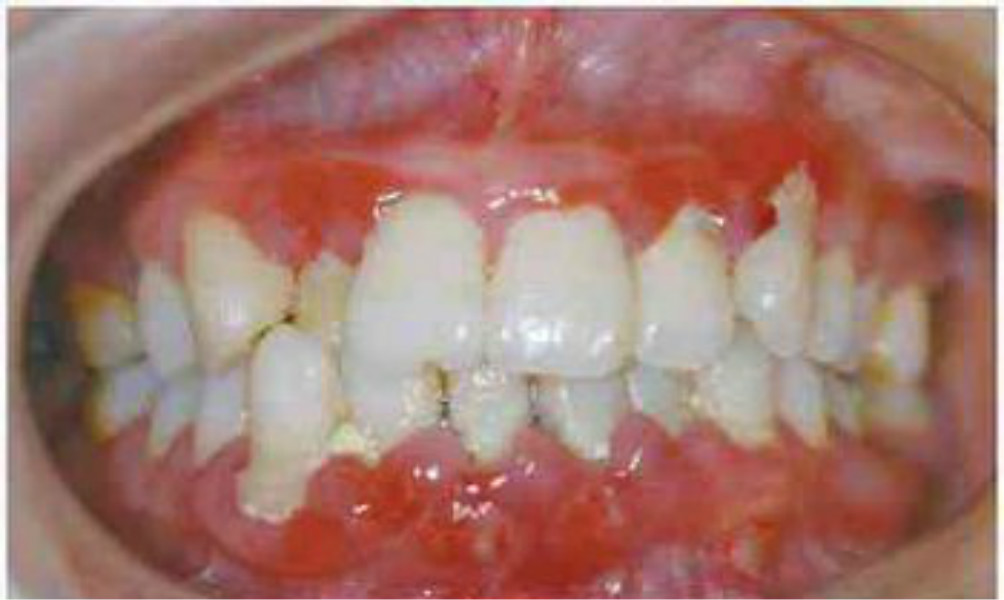

牙齦皮膚念珠菌病